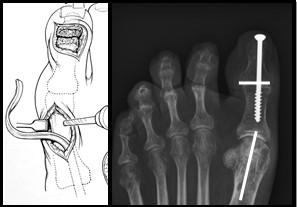

Figuur 4: Het bovenste linker plaatje is een schematische weergave van de “osteotomie”. Het driehoekje bij de pijl wijst naar de wig die uitgezaagd wordt. Het plaatje eronder laat de situatie zien na verwijderen van het wigje. Het middelste plaatje laat een voetfoto van een patiënt zien voor de operatie, de witte streep is de plaats van het litteken. het meest rechtse plaatje is na de operatie. Bij de pijl zie je de schroef en het ijzerdraadje om de botdelen op de juiste positie te houden.

Figuur 5: Op het linker plaatje is de grote teen zichtbaar. Er worden 2 littekens gemaakt. De pees wordt losgehaald bij het eindkootje en door het middenvoetsbeentje gevlochten door een boorgat. Op de rechter foto is de schroef zichtbaar die beide kootjes aan elkaar verbindt. Deze wordt vanuit het puntje van de teen geboord middels een (klein) 3e litteken. De witte streepjes geven de locatie van de andere 2 littekens aan.